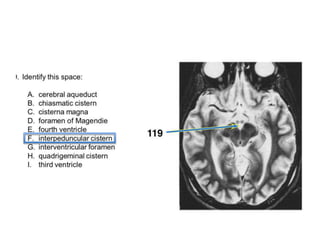

A. cerebral aqueduct

B. fourth ventricle

C. inferior cerebellar peduncle

D. interpeduncular fossa

E. middle cerebellar peduncle

F. oculomotor nerve

G. optic nerve

H. optic tract

I. prepontine cistern

J. third ventricle

K. trigeminal nerve

L. trochlear nerve

M. vagus nerve

N. vestibulocochlear nerve

What type of imaging is this?

A. CT with contrast

B. CT without contrast C. MRA

D. T1 MRI

E. T2 MRI